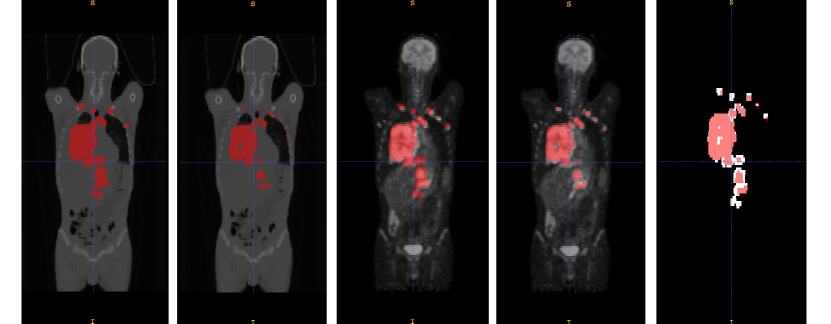

Although a lot of progress has been made in computer-aided lymphoma segmentation, the segmentation of whole-body lymphomas is still challenging. (Fig. 1 shows an example of lymphoma patient. There is great variation in intensity distribution, shape, type and number of lymphomas). The methods can be classified into three main categories: SUV-threshold-based [5], region-growing-based [4] and Convolutional Neural Network (CNN)-based [7] methods. For PET images, it is common to segment lymphomas with a set of fixed SUV thresholds. This method is fast but lacks of flexibility in boundary delineation and requires domain knowledge to locate the region of interest. Region-growing-based methods have been proposed to optimize boundary delineation by taking texture and shape information into account. However, those methods still need clinicians to locate the seeds for region growing [10].

Refer to caption

Figure 1: Examples of patient with lymphomas. The first and second rows show, respectively PET and CT, slices of one patient in axial, sagittal and coronal views. The lymphomas are marked in red.